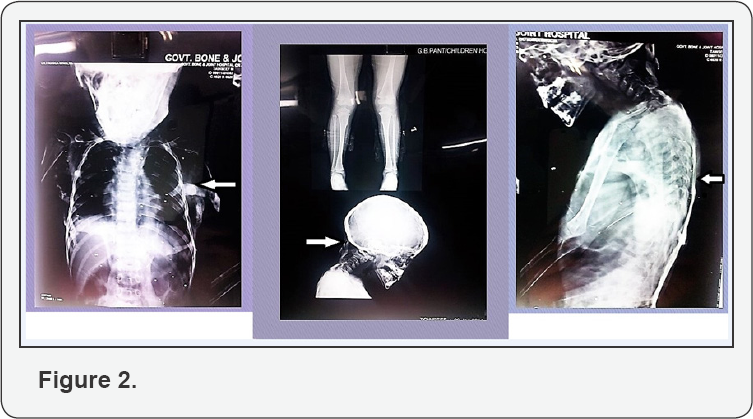

At admission, child had swellings involving entire back, shoulders and chest which were firm, non- tender, without redness or any signs of inflammation over the skin (Figure 1). Bilateral hallux valgus was noticed which is a hallmark of this disease (Figure 1). Skeletal radiographs show edextensive heterotopic ossifications in rib cage, spine and occipital region (Figure 2). Ultrasonography of swellings showed solid hypoechoic masses adhered to the rib cage and spine. Rest of the systemic examination was unremarkable. Other hematological and biochemical investigations revealed Hb- 12.7, TLC- 9,600/ cu mm (P44, L45, E09, M2), serum Calcium- 9.2 mg/dl; serum Phosphorus-5.4 mg/dl; CPK-57 IU/L, SGPT -28 IU/ L; and alkaline phosphatase-40 KAU. ECG was normal.

The radiological skeletal survey revealed extensive heterotopic ossification in neck, thoracic walls, back, upper limbs and hips with bone deformities (Figure 2). CT thorax showed multiple plaque-like calcifications involving the pectoralis major and para-spinal muscles (Figure 3). Diagnosis of FOP was strongly considered. Blood samples of both the parents and child were collected for sequencing the activing receptor IA (ACVR1) gene. A heterozygous mutation(617 G>A; q.R206H), which is the most common mutation reported to be associated with FOP, was detected in the child confirming the diagnosis As there were no acute flare-ups, no NSAID's or steroids were given. The child was given graded physiotherapy and parents were explained the nature of ailment with precautions to prevent trauma (particularly iatrogenic injury from intra-muscular injections, biopsies, and surgery) and trivial injuries inflicted during playful activities.